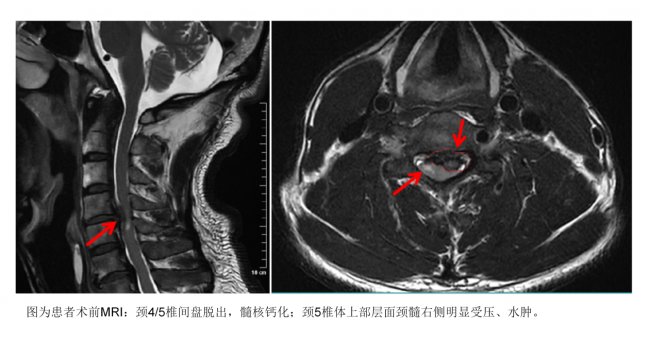

西南地区首例!四川泰康医院成功实施美敦力新型人工椎体手术

2月2日上午,四川泰康医院神经外科病房,几天前还走路不便,需要搀扶的52岁患者陈先生(化名)没有依靠助步器,也不用人搀扶,高兴地在病房里走了两圈。因为今天是他出院的日子,高兴的他恨不得一直走个不停。